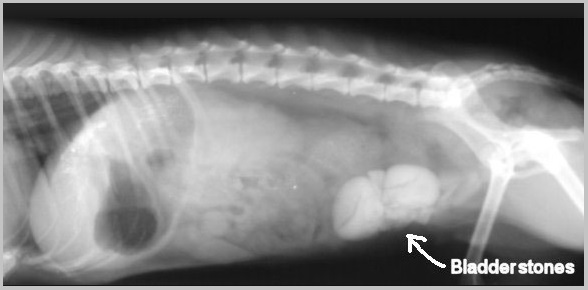

Hyperuricosuria is an inherited condition of the urinary system affecting several breeds of dog. The SLC2A9 gene codes for a protein that allows the kidneys to transport uric acid from the urine. Dogs with mutations in both copies of the SLC2A9 gene are predisposed to have elevated levels of uric acid in the urine, hence the name hyperuricosuria. Uric acid can form crystals and/or stones (uroliths) in the urinary tract. Dogs with hyperuricosuria most commonly present with symptoms of recurrent urinary tract inflammation, which include frequent urination, blood in the urine, and straining to urinate. They may also have loss of appetite, lethargy, weakness, vomiting and pain. Urinary stones in the bladder can cause urinary tract infections or more seriously, blockage of the Urethra. Both male and female dogs can be affected, but obstruction of urine flow is more common in males due to differences in anatomy. Although an x-ray can be used to exclude other types of stones, urate stones cannot typically be seen using x-rays and must be evaluated by ultrasound. Not all dogs with mutations in both copies of the SLC2A9 gene will have symptoms of disease, though they will have increased uric acid excretion in the urine.